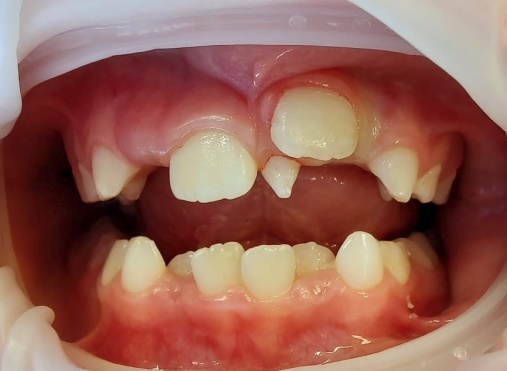

Việc kiểm soát tình trạng răng mọc chậm do răng thừa có thể được thực hiện bằng hai phương pháp. Thứ nhất, bằng cách điều trị bảo tồn, chỉ bằng cách phẫu thuật loại bỏ răng thừa (hình 4). Thứ hai, bằng cách phẫu thuật loại bỏ răng thừa kết hợp cùng lúc với chỉnh nha kéo răng cửa ngầm lên (hình 5).

R21 chưa mọc, R11 đã mọc (a), Răng thừa (b), R22 (c) (b)Răng thừa thứ nhất, (a) răng thừa thứ 2, (c) R21 ngầm chưa mọc Phẫu thuật lật vạt:(a) răng thừa thứ 1, (b) R21 ngầm, (c) R22

image 20231218155055 19 502x340

Răng thừa thứ 1đã được nhổ Bộc lộ răng thừa thứ 2 Hình ảnh 2 răng thừa

Hình ảnh sau phẫu thuật 6 tháng, R21 đã mọc lên sau khi loại bỏ 2 răng thừa

Hình 4: Minh họa cho phẫu thuật lấy răng thừa đơn thuần ở một bé trai 9 tuổi